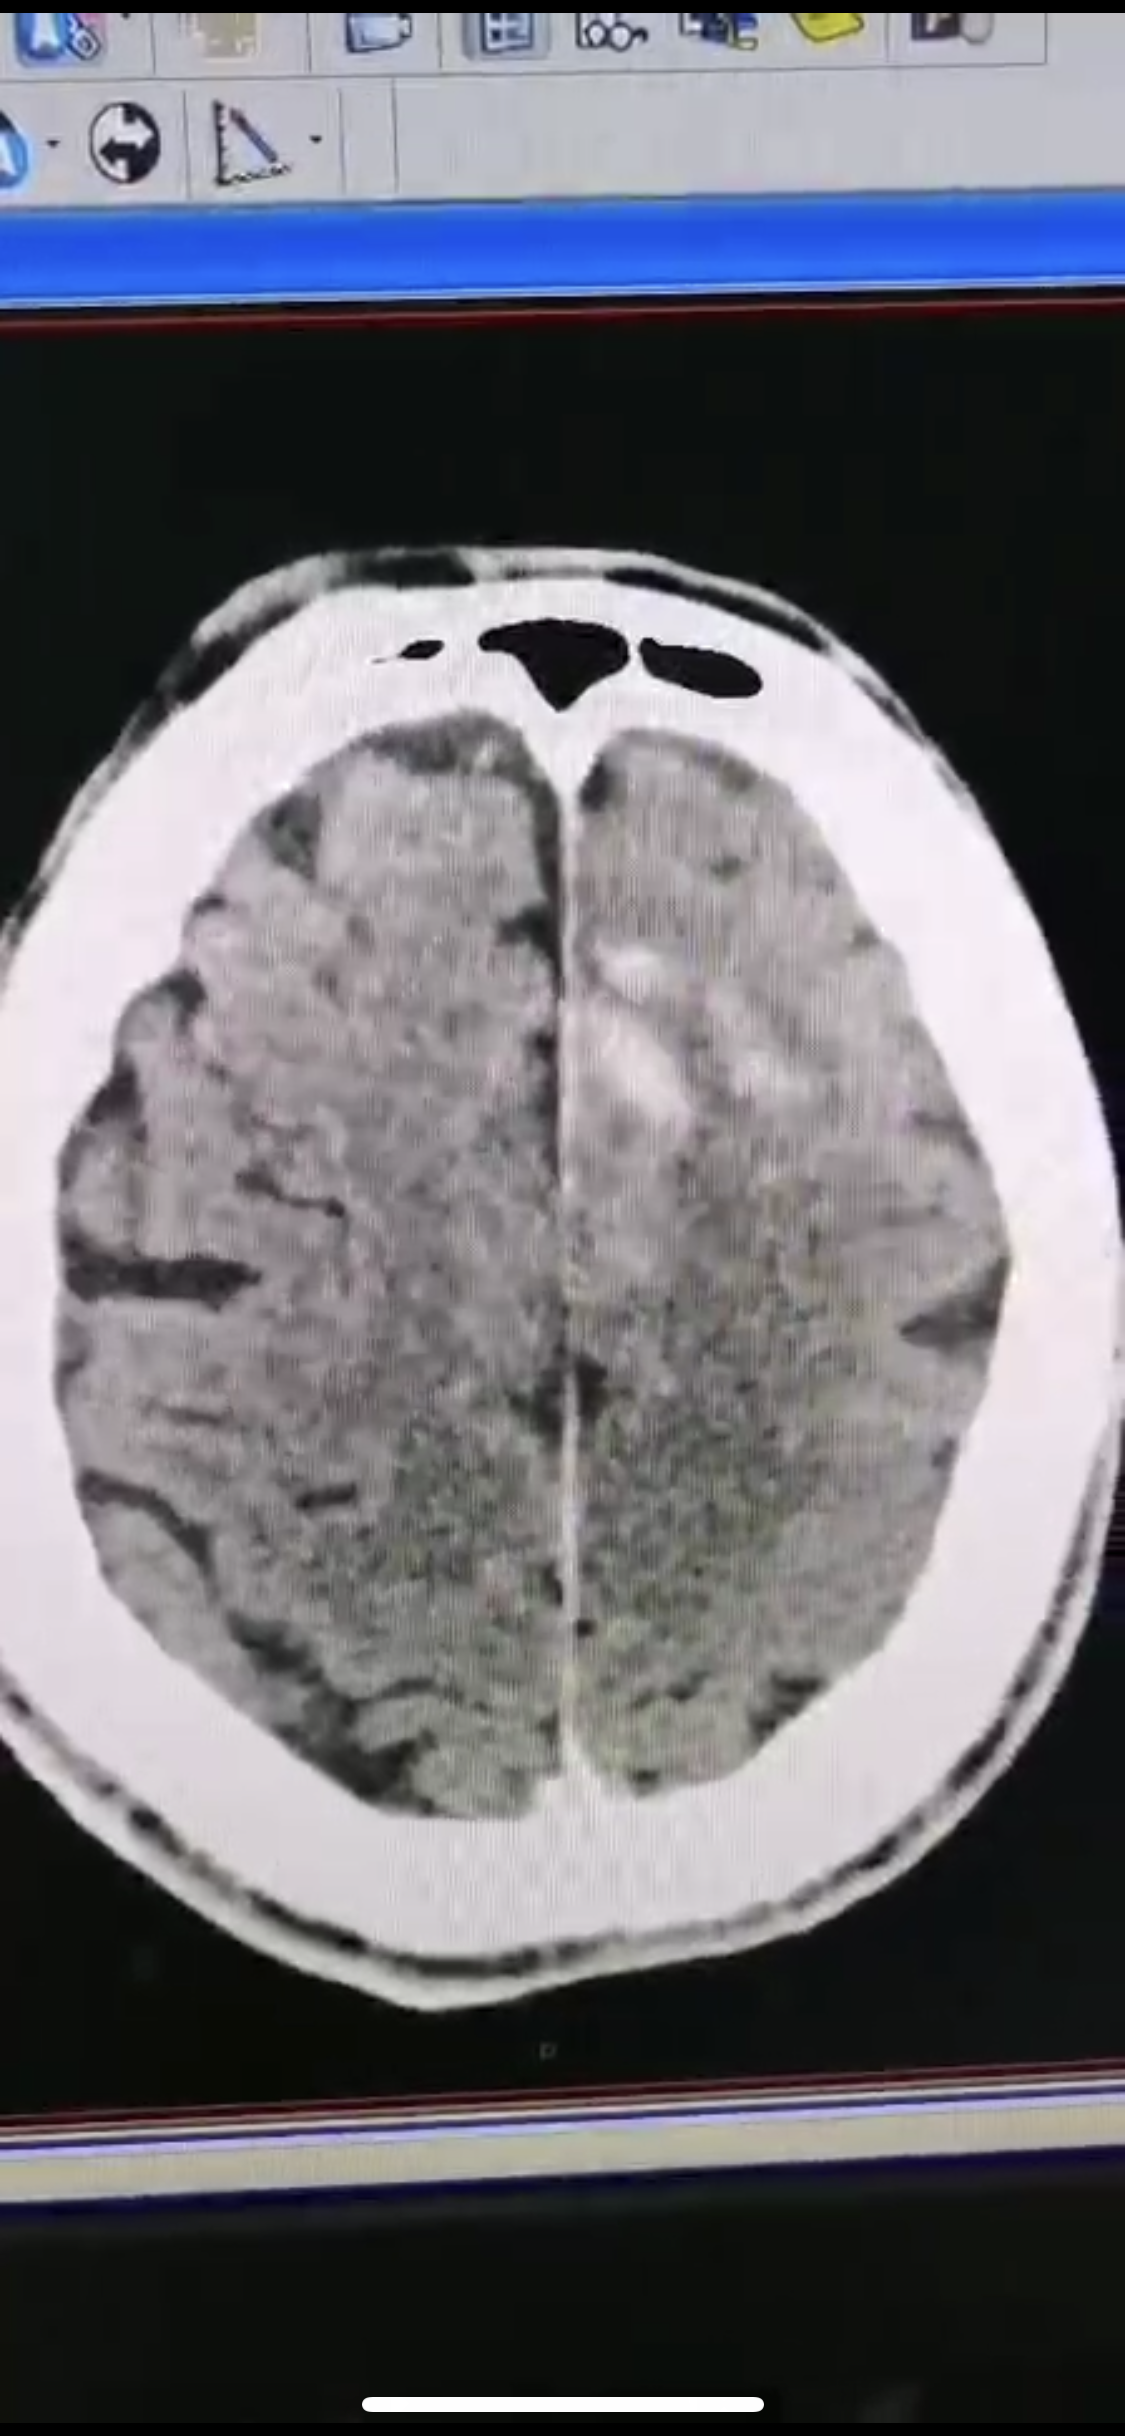

急诊二。zde,f53y。

意识模糊进行性加重8h,基底动脉闭塞,reco取栓再通,貌似动脉硬化,实际血管光滑。造影➕取栓8min。今日团队配合紧密,不到三小时全麻造影取栓带苏醒完成两台取栓。团队棒棒的!南阳市中心医院神经内科脑血管病介入团队